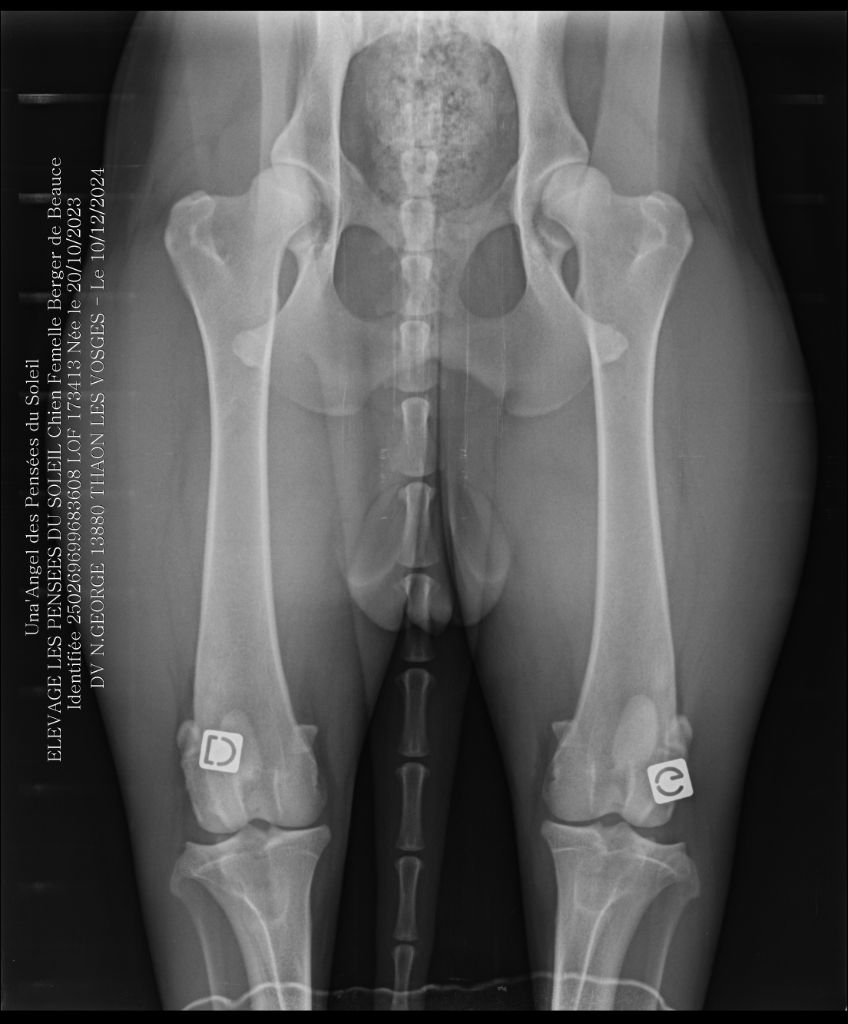

Una'angel Les Pensées Du Soleil

femelle

Berger de Beauce

née le

20/10/2023

| Puce | 250269699683608 |

| N° origine | 173413/24661 |